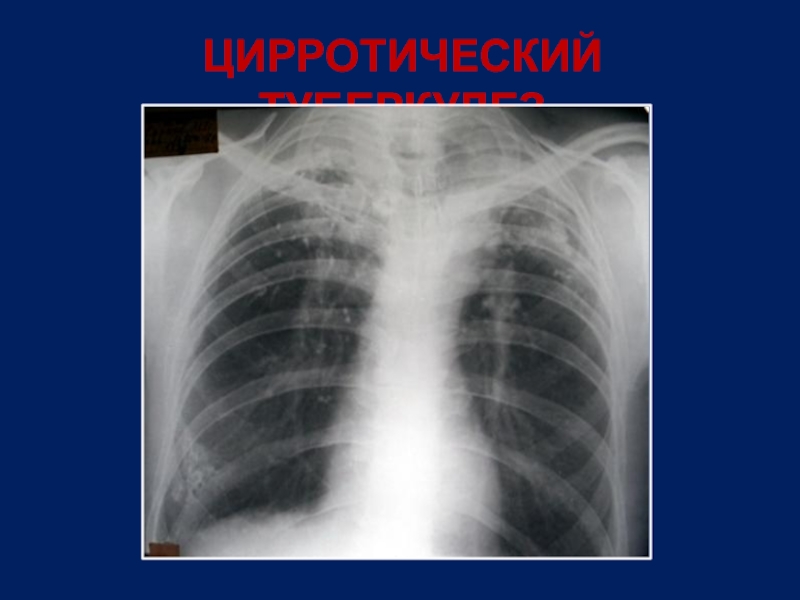

Слайд 24ЦИРРОТИЧЕСКИЙ ТУБЕРКУЛЕЗ

Затемнение высокой интенсивности с уменьшением объема легкого

Плотные включения и кальцинаты

Локализация

– верхние отделы легких

Смещение корня и средостения в сторону цирроза

Эмфизема базальных отделов

В клинике преобладают симптомы дыхательной

недостаточности, хр.неспецифического воспаления

Активность туберкулезного процесса невысокая

МБТ в мокроте непостоянно

Наличие в мокроте неспецифической флоры

Слайд 25ЦИРРОТИЧЕСКИЙ ТУБЕРКУЛЕЗ

Слайд 26ЦИРРОТИЧЕСКИЙ ТУБЕРКУЛЕЗ

Слайд 27ЦИРРОТИЧЕСКИЙ ТУБЕРКУЛЕЗ